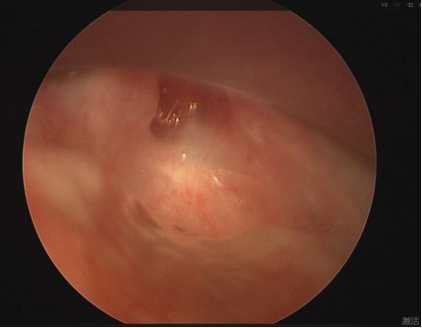

声门完全闭锁手术难度非常大

用进废退,来到南方医科大学深圳医院儿童耳鼻咽喉科时,丁丁已从「声门下狭窄」,变成「声门下主气管完全闭锁」,属于最严重的那种。

本来应该是个洞,如今已成一堵墙,能说话才有鬼呢。

▲ 声门下完全闭锁